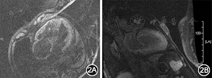

血常规:白细胞8.0×109/L,红细胞4.35×1012/L,血红蛋白125 g/L,血小板71×109/L,嗜中性粒细胞百分比80.4%;尿常规未见异常;肾功能:尿素氮11.9 mmol/L,肌酐107.8 μmol/L,尿酸471 μmol/L;N末端B型利钠肽原(NT-proBNP):2 101 ng/L(正常值<125 ng/L);D二聚体1 618.1 μg/L;甲状腺功能正常;肌钙蛋白I 0.15 μg/L(正常值<0.04 μg/L),肌酸激酶(CK)和肌酸激酶同工酶(CK-MB)在正常范围;红细胞沉降率7 mm/h;尿β2微球蛋白6.60 mg/L(正常值0~0.37 mg/L),尿微量白蛋白22.8 mg/L(正常值0~22.5 mg/L),血β2微球蛋白3.20 mg/L(正常值0.97~2.64 mg/L);血清蛋白电泳:清蛋白51.12%(正常值55.00%~68.00%),α1球蛋白8.16%(正常值1.00%~5.70%),α2球蛋白18.41%(正常值4.90%~8.80%),β球蛋白16.73%(正常值5.70%~10.40%),γ球蛋白5.58%(正常值9.80%~20.00%);血清免疫固定电泳:免疫球蛋白G升高,轻链κ升高;尿本周蛋白测定:轻链定量κ 0.040 g/L(正常值0~0.019 g/L),轻链定量λ<0.050 g/L(正常值0~0.050 g/L)。心电图示心房颤动,心室率78次/min,肢体导联低电压,右束支传导阻滞。肘静脉压力:右侧肘静脉压力为25 cmH2O(1 cmH2O=0.098 kPa),压肝后压力为35 cmH2O。发病2年以来,系列超声心动图示室壁逐渐增厚(图1),入院后超声心动图示左心房、右心房、右心室增大,左心室不大,左心房前后径36 mm,右心房内径45 mm×58 mm,右心室前后径31 mm,左心室舒张末期最大前后径37 mm,左心室壁弥漫性增厚,左心室后壁厚度16 mm,室间隔厚度19 mm,右心室壁厚度7 mm,室壁回声呈毛玻璃样,左心室壁弥漫性运动减弱,二尖瓣关闭不全(轻度),三尖瓣关闭不全(重度),主动脉瓣关闭不全(轻微),左心室收缩和舒张功能减退,左心室射血分数28%,少量心包积液。心脏磁共振及钆延迟增强扫描示:右心房和右心室增大,左右心室壁增厚;黑血序列显示左右室心肌内可见散在斑点状高信号影;延迟增强扫描可见右心房、室间隔、左右心室心肌呈弥漫性强化(图2)。腹部皮肤及皮下脂肪组织活检(图3):皮下纤维细胞增生,玻璃样变;纤维、血管壁及脂肪组织可见刚果红染色阳性的特殊物质沉积,不除外淀粉样变性。骨髓活检:刚果红染色阴性。骨髓细胞学检查:骨髓增生明显活跃,浆细胞比例偏高(占7.5%),排除多发性骨髓瘤。本病例确诊为免疫球蛋白轻链型心脏淀粉样变性,住院期间给予利尿和改善心功能治疗后,症状有所缓解,NT-proBNP较前无明显降低。

心脏淀粉样变性的特点:(1)临床表现[1]:早期为心脏舒张功能障碍,以后发展至限制型心肌病,有右心衰竭的症状和体征,如颈静脉压增高、右心室奔马律、肝脏肿大和外周水肿,部分患者发展为难治性充血性心力衰竭。(2)心电图特点[1]:表现为标准肢体导联低电压和胸前导联R波递增不良(类似于恢复期前间壁心肌梗死波形),常伴有心房颤动和传导阻滞。(3)超声心动图特点[1]:表现为心室壁和室间隔明显对称性肥厚,左心室心腔正常或缩小,左心室舒张功能减退;同时,心肌特征性回声增强,呈颗粒状闪烁样表现;此外,还可有心房扩大、瓣膜增厚或反流、心包积液、晚期伴有心室充盈压增高的限制性表现。(4)心脏磁共振特点[2]:弥漫性和(或)透壁性钆延迟强化。(5)核素:心肌99Tcm焦磷酸盐闪烁照相表现为同位素浓集的阳性影像(因99Tcm焦磷酸盐可以结合到与淀粉样纤维相关的钙分子上)。(6)组织活检[1]:心内膜活检是心脏淀粉样变性最直接的确诊方法,但取材困难。鉴于淀粉样变性为全身性疾病,多累及全身各个部位,故临床上可以采用心肌外活检代替心肌活检。如果在心脏以外活检发现淀粉样物质沉积,结合超声心动图和心电图特征性改变,也可确诊,无需再做心内膜活检。皮下脂肪垫活检结合骨髓刚果红染色对淀粉样变性患者的组织学诊断率达90%。刚果红染色在偏光下产生苹果绿样折射,是淀粉样变性最特异的染色。另外,也可在电子显微镜下观察淀粉样物质沉积。

心脏淀粉样变性是淀粉样物质沉积于心脏,造成心脏结构及功能的改变。淀粉样物质在心肌组织沉积可导致向心性左心室肥厚,心肌顺应性下降,甚至舒张功能障碍,最终引起收缩功能障碍。不同阶段的心脏淀粉样变性患者临床表现各异,缺乏特异性表现,容易误诊为其他类型的心肌病,尤其需要与肥厚型心肌病或高血压引起的心肌肥厚鉴别。心电图肢体导联电压均较低,与超声心动图中室间隔和左心室后壁厚度增加呈反比关系,这一点与高血压引起的心室肥厚和肥厚型心肌病截然不同;后二者随着室壁厚度增加,心电图肢体导联电压亦相应增加[3]。心脏淀粉样变性的典型磁共振钆延迟增强扫描显示为弥漫性钆延迟强化图像,而肥厚型心肌病钆延迟扫描为肥厚心肌内斑片样钆延迟强化。